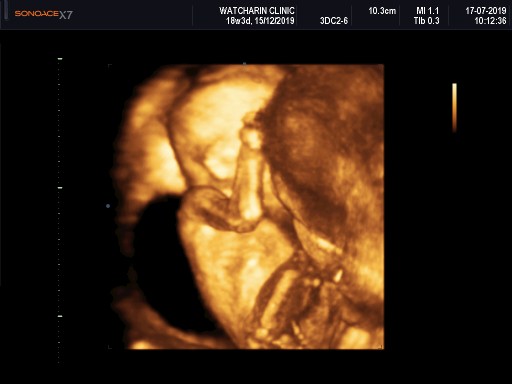

ภาพซาวด์ 4เดือนครึ่งคะ ผญ.